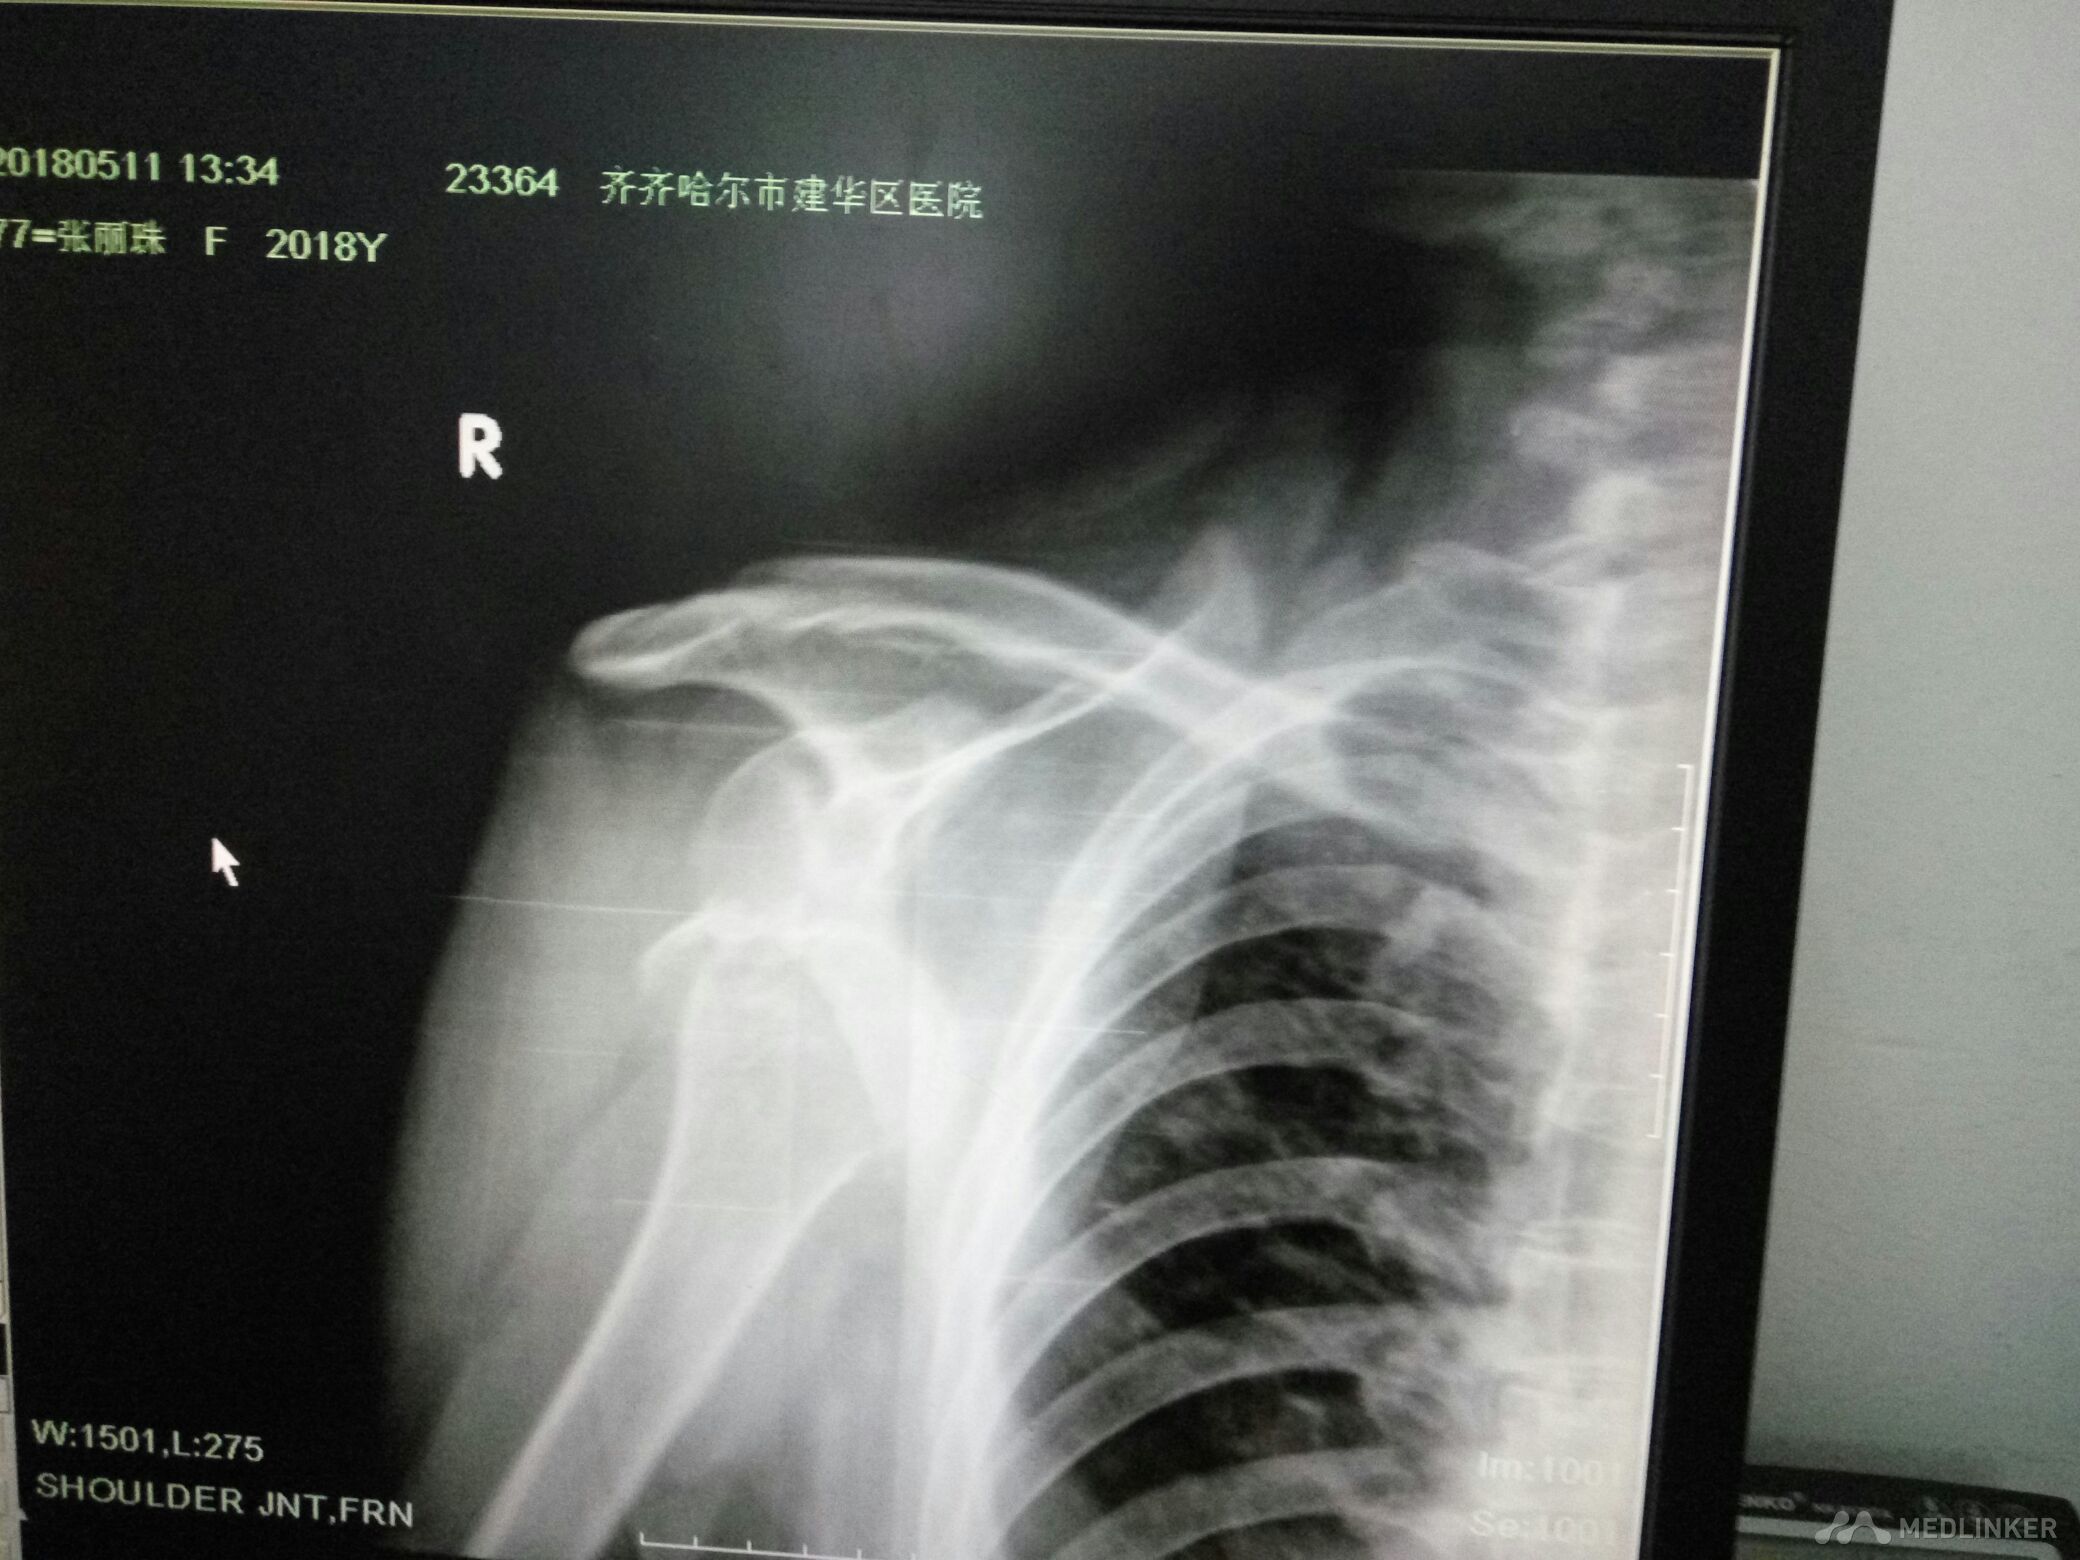

右肩关节脱位并肱大结节撕脱性骨折

该患者女77岁不慎跌倒所致肩关节活动丧失局部疼痛来齐齐哈尔市解放门医院骨科经张立群医生诊断肩关脱位拍片检查右肩关节脱位并肱骨大结节骨折经手法整复后拍片检查复位成功肱骨大结节骨折对位对线良好。